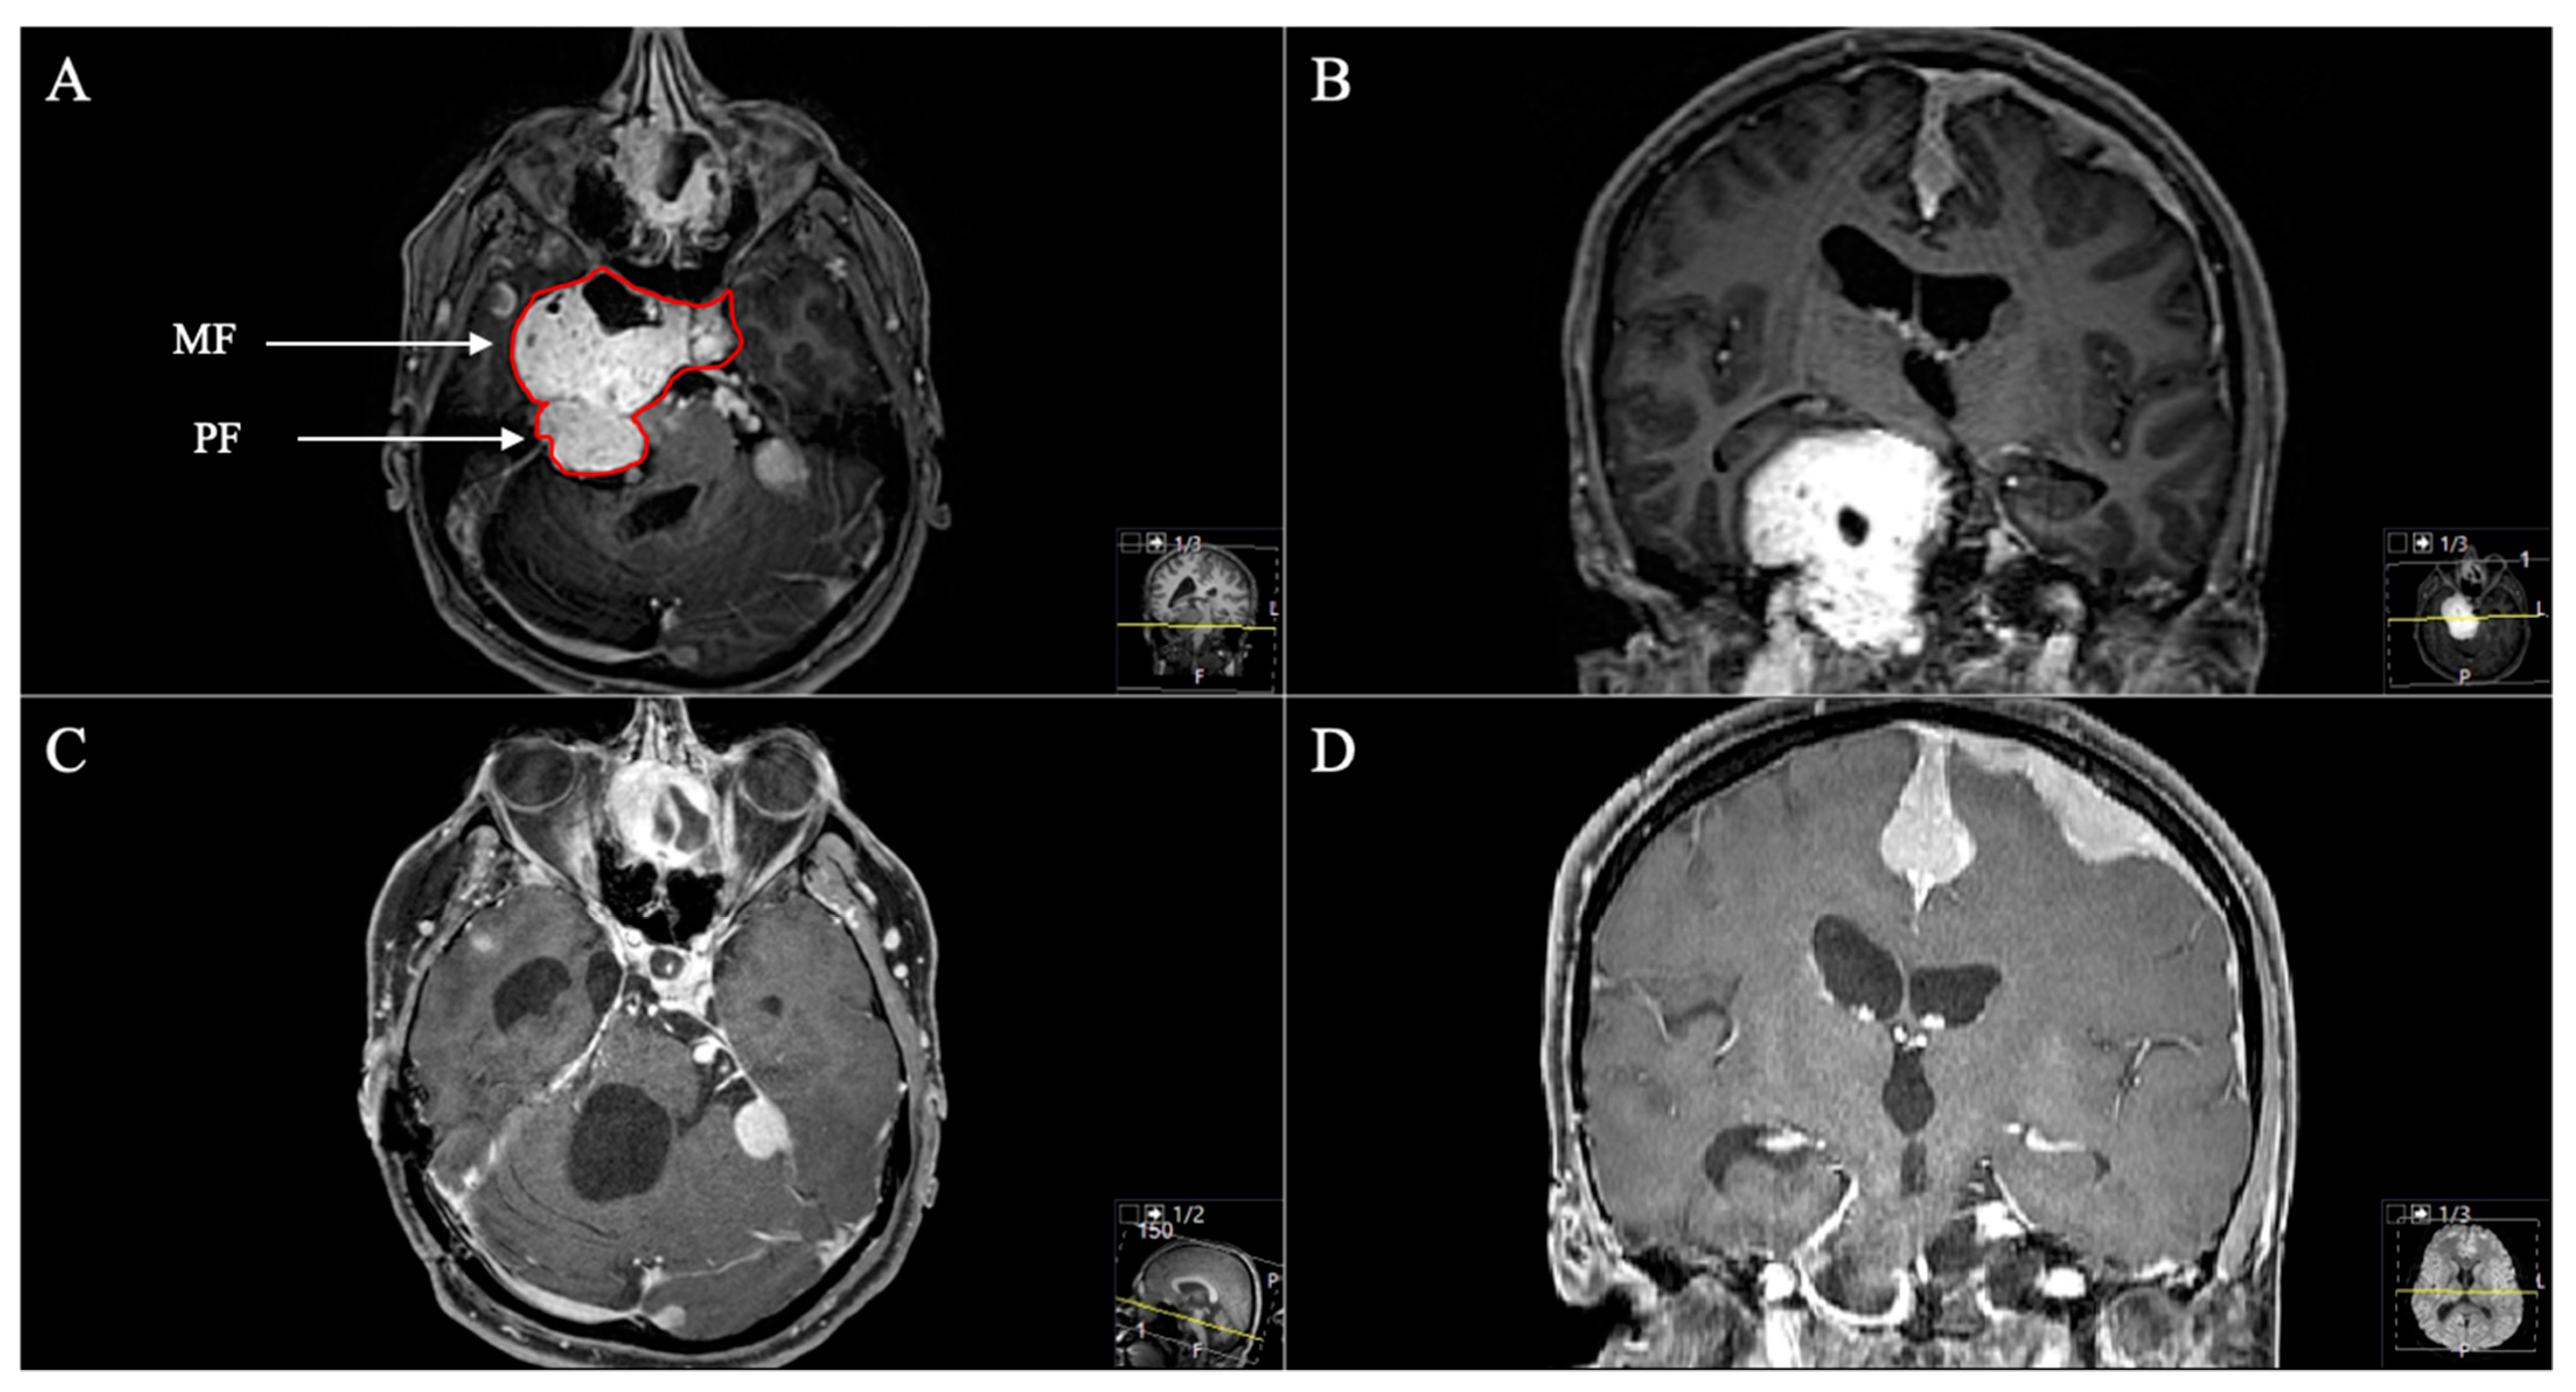

Figure 6. A 53-year-old female patient presented with vomiting, slight ataxia, facial pain and trigeminal hypesthesia (V1,V2) for three months. (A) Preoperative axial and (B) coronal T1-weighted gadolinium-enhanced MRI, showing a space-occupying cystic trigeminal schwannoma invading the cerebellopontine angle (Samii Type B). (C) Postoperative axial and (D) coronal MRI control, indicating complete resection via a retrosigmoid approach. Postoperatively, new temporary slight hypoacusis and facial neve palsy (House and Brackmann Grade III) occurred.